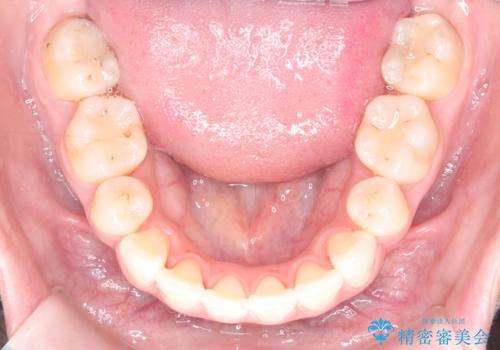

精密検査の結果、歯を後方へ下げるためのスペースが不足していたため、上下左右の4番目の歯(第一小臼歯)を計4本抜歯する計画を立案しました。抜歯によってできたスペースを最大限に活用し、前歯を後ろに下げることで、口元のボリュームを抑え、バランスの良いEライン(横顔のライン)を目指すこととしました。装置は、日常生活で目立ちにくい審美ワイヤーを選択しました。

治療は、審美ワイヤーを用いて抜歯スペースを徐々に閉じながら、前歯の角度と位置を精密にコントロールして進められました。ワイヤー矯正は歯を三次元的にしっかりと動かすことができるため、前歯を単に倒すのではなく、根元から理想的な位置へと誘導しました。

1年半の治療期間を経て、抜歯したスペースは完全に閉じ、突き出ていた前歯はすっきりと内側に収まりました。噛み合わせの精度も向上し、機能面でも良好な結果が得られています。

治療完了後、口元の突出感が解消されたことでお顔全体の印象がシャープになり、患者様からも大変満足していただくことができました。目立ちにくい装置を使用したことで、1年半という期間も無理なく継続し、理想的なゴールを迎えることができました。